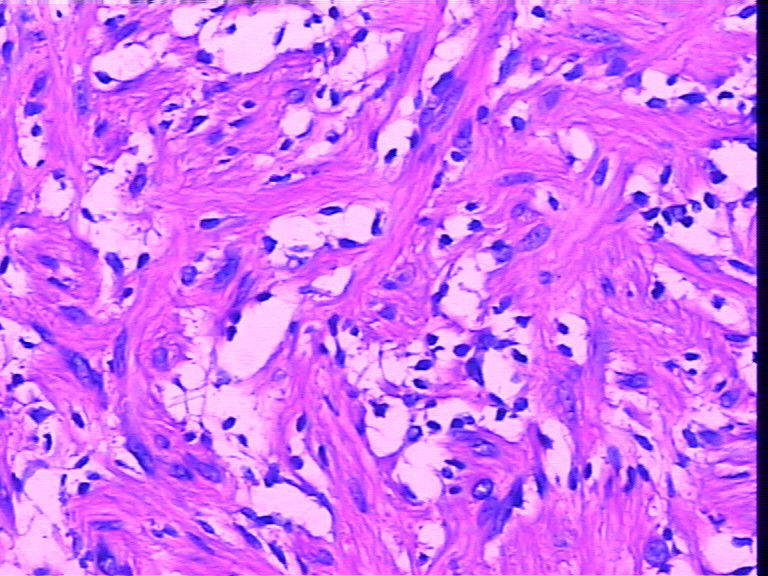

腹壁一个包块,大小4cmx2cmx2cm,椭圆形,有菲薄包膜,淡黄色,切面淡黄色半透明,质地偏韧。

是女性患者,19岁。考虑为神经方面肿瘤,等着病人过来加做免疫组化。

梭形细胞肿瘤

1、SFT

2、梭形细胞血管内皮瘤

3、神经源性肿瘤如神经鞘瘤,神经纤维瘤

4、纤维组织细胞瘤

5、平滑肌瘤

感觉首先是孤纤和神经纤维瘤(图3很像,但是有包膜,神经鞘需要考虑)鉴别。

梭形细胞血管内皮瘤大小不太符合,其大多发生在四肢,临床大体多为紫红色小结节。主要由海绵状血管瘤和梭形细胞区域组成。1.看不到海绵状的血管瘤区域;2.在梭形细胞区域我们看不到部分呈上皮样的血管内皮细胞,3.的确在间质内可见空泡(似原始管腔),但是不见红细胞。可以作为鉴别诊断,但是不首先考虑。